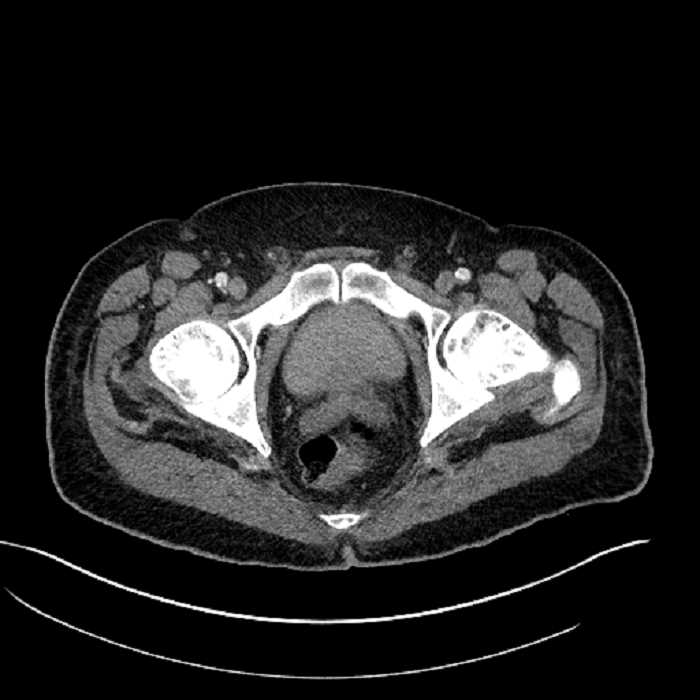

• Mild mural thickening of a segment of the sigmoid colon with adjacent fat stranding and a 1.5 cm fluid and gas collection along the tip of an inflamed diverticulum

• Loss of the normal fat plane between this collection and adjacent loops of small bowel, which demonstrate mural thickening

• No bowel obstruction

Acute sigmoid diverticulitis complicated by a small contained perforation and a large abscess in the right hepatic lobe. Additional small subcapsular abscesses along the anterior margin of the left hepatic lobe.

Additionally, loss of the normal fat plane between the peridiverticular collection and adjacent thickened loops of small bowel raises the potential for an enterocolonic fistula.

Hepatic abscess showing the double target sign with low density internally surrounded by a thin inner enhancing rim (red arrow) and ill-defined outer low density rim (yellow arrow). Blue arrow indicates an internal septation. Red arrows: additional smaller subcapsular abscesses. Red arrow: focal contained perforation associated with diverticulitis.